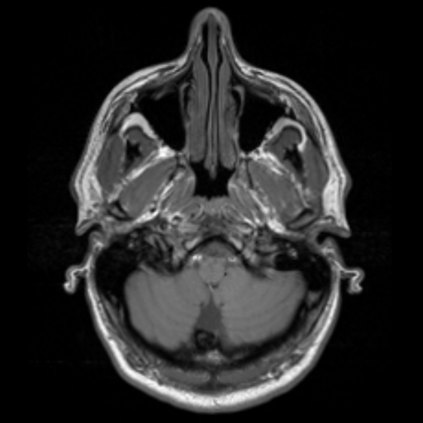

Motion artifacts are a primary source of magnetic resonance (MR) image quality deterioration with strong repercussions on diagnostic performance. Currently, MR motion correction is carried out either prospectively, with the help of motion tracking systems, or retrospectively by mainly utilizing computationally expensive iterative algorithms. In this paper, we utilize a novel adversarial framework, titled MedGAN, for the joint retrospective correction of rigid and non-rigid motion artifacts in different body regions and without the need for a reference image. MedGAN utilizes a unique combination of non-adversarial losses and a novel generator architecture to capture the textures and fine-detailed structures of the desired artifacts-free MR images. Quantitative and qualitative comparisons with other adversarial techniques have illustrated the proposed model's superior performance.

翻译:移动文物是磁共振(MR)图像质量恶化的一个主要来源,对诊断性能产生强烈影响。目前,MR运动的校正要么是预期性的,借助运动跟踪系统,要么是追溯性的,主要是利用成本昂贵的计算迭代算法。在本文中,我们使用名为MedGAN的新颖的对抗性框架,联合追溯性地校正不同身体区域的硬性和非硬性运动文物,而不需要参考图像。 MedGAN利用非对抗性损失和新型生成器结构的独特组合来捕捉无MR图象的纹理和精细详细结构。 与其他对抗性技术的定量和定性比较展示了拟议模型的优异性表现。